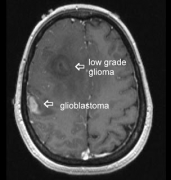

低级别胶质瘤能恶化成高级别胶质瘤吗?低级别胶质瘤 是由WHO分级系统划分为I级和II级的原发性脑瘤,主要发生于儿童和年轻人。较常见的低级别胶质瘤是...

低级别胶质瘤的手术时机怎么选?术后是否需要放化疗?什么情况容易恶化为高级比胶质瘤?预后生存期如何?有哪些争议?一文深入解读,一探究竟。...

弥漫性低级别胶质瘤(LGG)是一种异质性的脑肿瘤,其病理的自然历史特征是沿着白质通路缓慢而持续的生长,从而导致固有的高复发和恶变倾向。偶发性低...